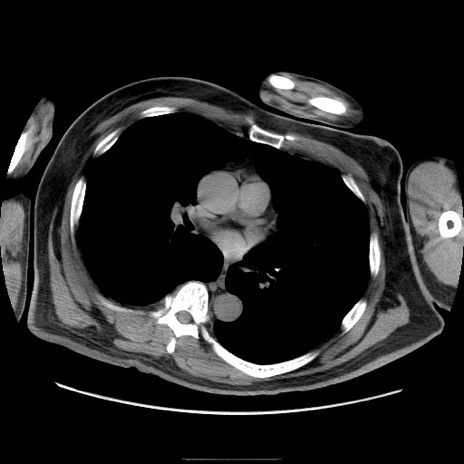

冠状断像

【症例】50歳代男性

【主訴】腹痛

【現病歴】AVMからの被殻出血のため回復期リハ病棟入院中。 本日午後3時頃急に下腹部痛が出現した。

【既往歴】AVM、被殻出血、虫垂炎、高血圧

【身体所見】意識晴明、左半身不全麻痺、会話の理解は良好、36.5°C、腹部:膨隆、全体に板状硬、下腹部正中に圧痛点あり、反跳痛-、筋性防御不明、右下腹部にope scar

【データ】WBC 9400、CRP 0.06